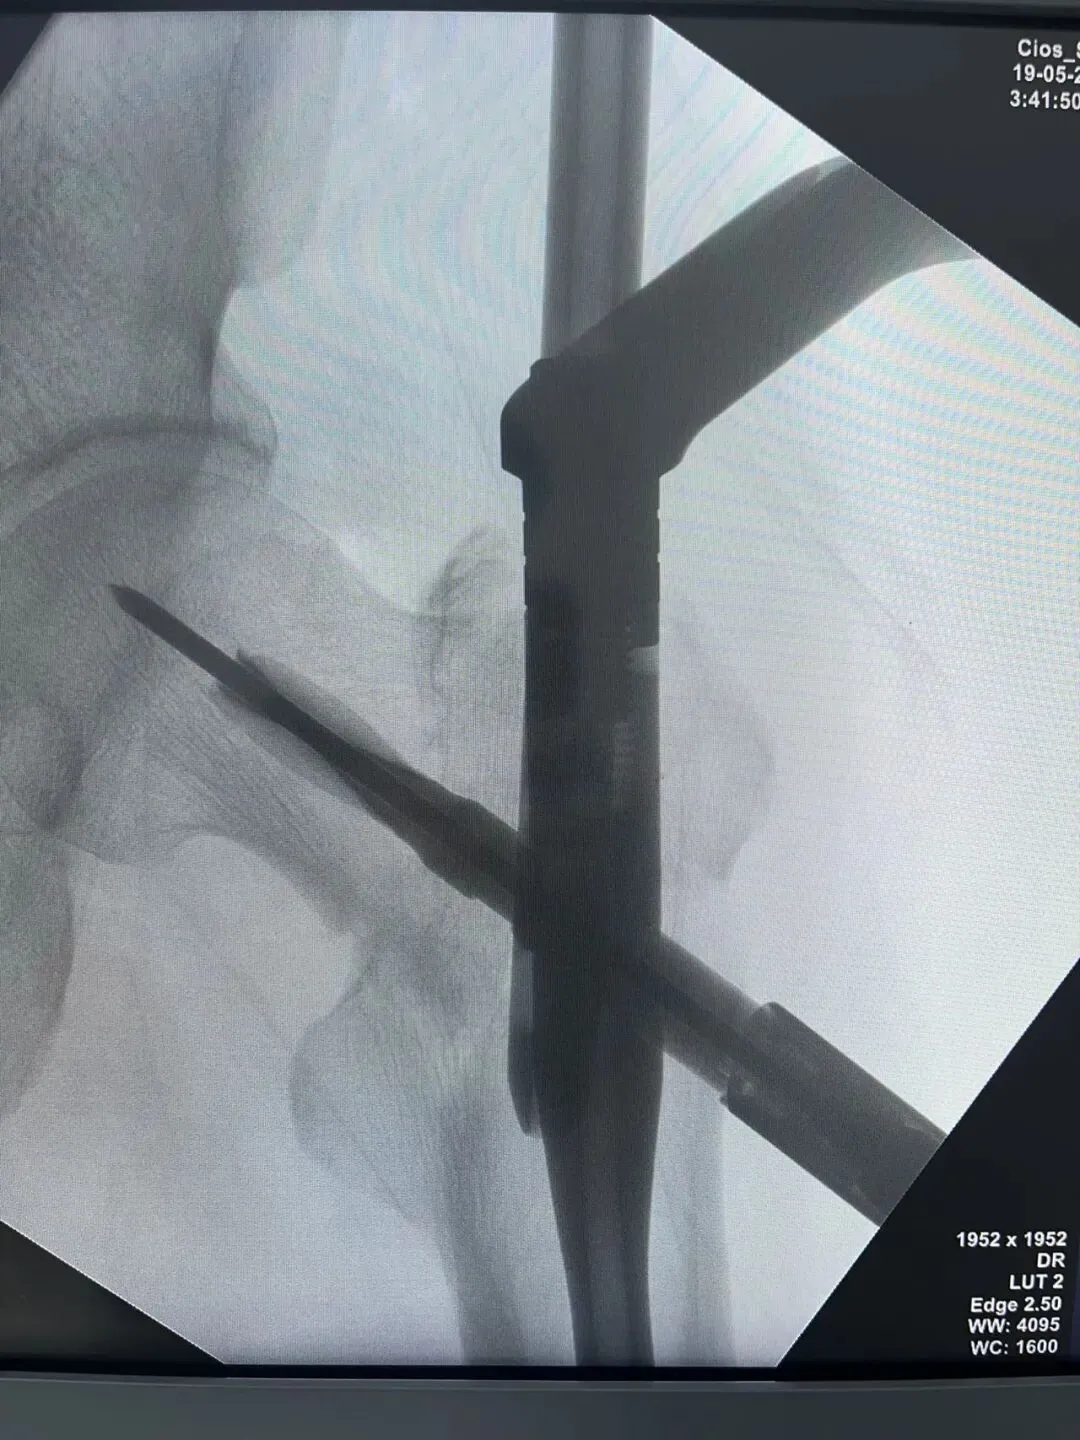

先看片子

中老年男性,高处坠落伤,如此长节段股骨近端骨折比较少见。手术治疗是必须的,患者等待期间血栓风险极高。而且患者卧床骨牵引期间护理极其不方便,给家人造成很大困惑为早点解决患者病痛,入院后积极抗凝预防血栓,伤后第3天手术治疗。我们选择PFNA闭合复位内固定。手术还算顺利。

手术在牵引床上操作,近端开口器开口后用金手指找远折端,找到后顺势插入导针,剩下的就是套路了。如此长节段的股骨近端骨折,一定要做到闭合复位,保证骨折周围软组织铰链夹板完整,不破坏局部血运,才能保证骨折的顺利愈合。